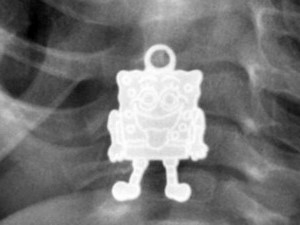

Raio-X mostra pingente do Bob Esponja na garganta de criança de 1 ano